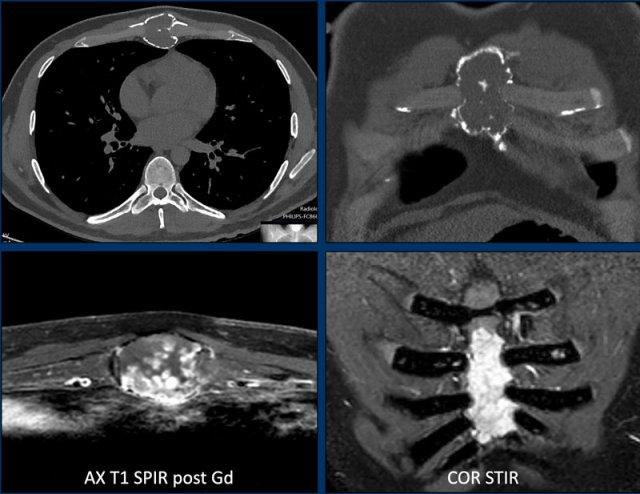

Hình ảnh

CT axial cho thấy một khối u tiêu xương dạng膨胀 tại thân xương ức.

Có nhiều ổ phá hủy vỏ xương.

Vôi hóa dạng bỏng ngô hiện diện ở trung tâm.

MRI xác nhận bản chất sụn của khối u này với tín hiệu tăng sáng trên ảnh STIR và ngấm thuốc tương phản dạng vách-nốt.

Kết luận

Mặc dù không có thành phần mô mềm, do sự giãn rộng và nhiều ổ phá hủy vỏ xương, khối u này nên được gọi là sarcoma sụn độ II hoặc cao hơn và cắt bỏ khối là phương pháp điều trị đúng đắn.

Pathology showed a grade II

chondrosarcoma.

Trong bộ xương trục, các khối u sụn có tiên lượng xấu hơn.

Điều này có nghĩa là chúng sẽ được phẫu thuật cắt bỏ ngay cả khi ở độ I, khác với khối u cùng loại ở bộ xương ngoại vi, được gọi là ACT và sẽ được theo dõi.

Không được gọi các khối u ở bộ xương trục là u sụn nội xương nếu chúng có dấu hiệu xói mòn vỏ xương hoặc phá hủy vỏ xương, vì điều này có thể dẫn đến điều trị không đầy đủ.